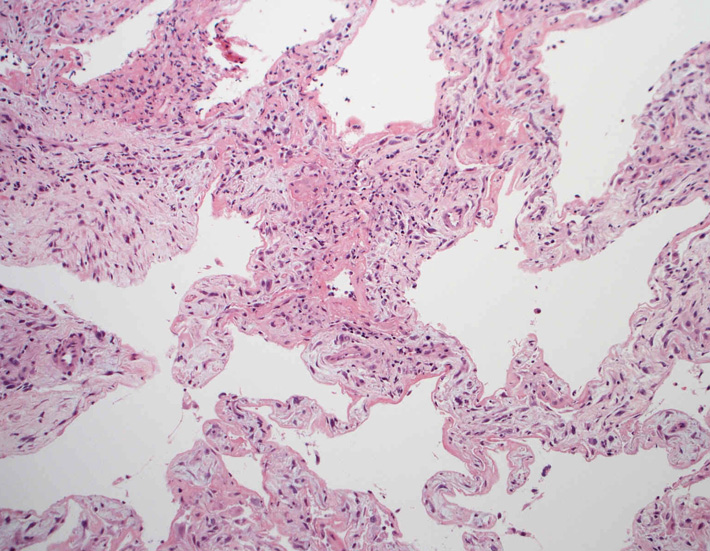

肺毛細血管炎 capillaritis

肺胞壁に多数の好中球浸潤。肺胞腔内に出血。 capillaritisが起こるWegener' granulomatosis劇症型には, なかなか肉芽腫性病変を見つけることは難しい

capillaritisの組織所見*17

Fig.01 capillaritisと肺胞出血Fig.02 Fig.01拡大像